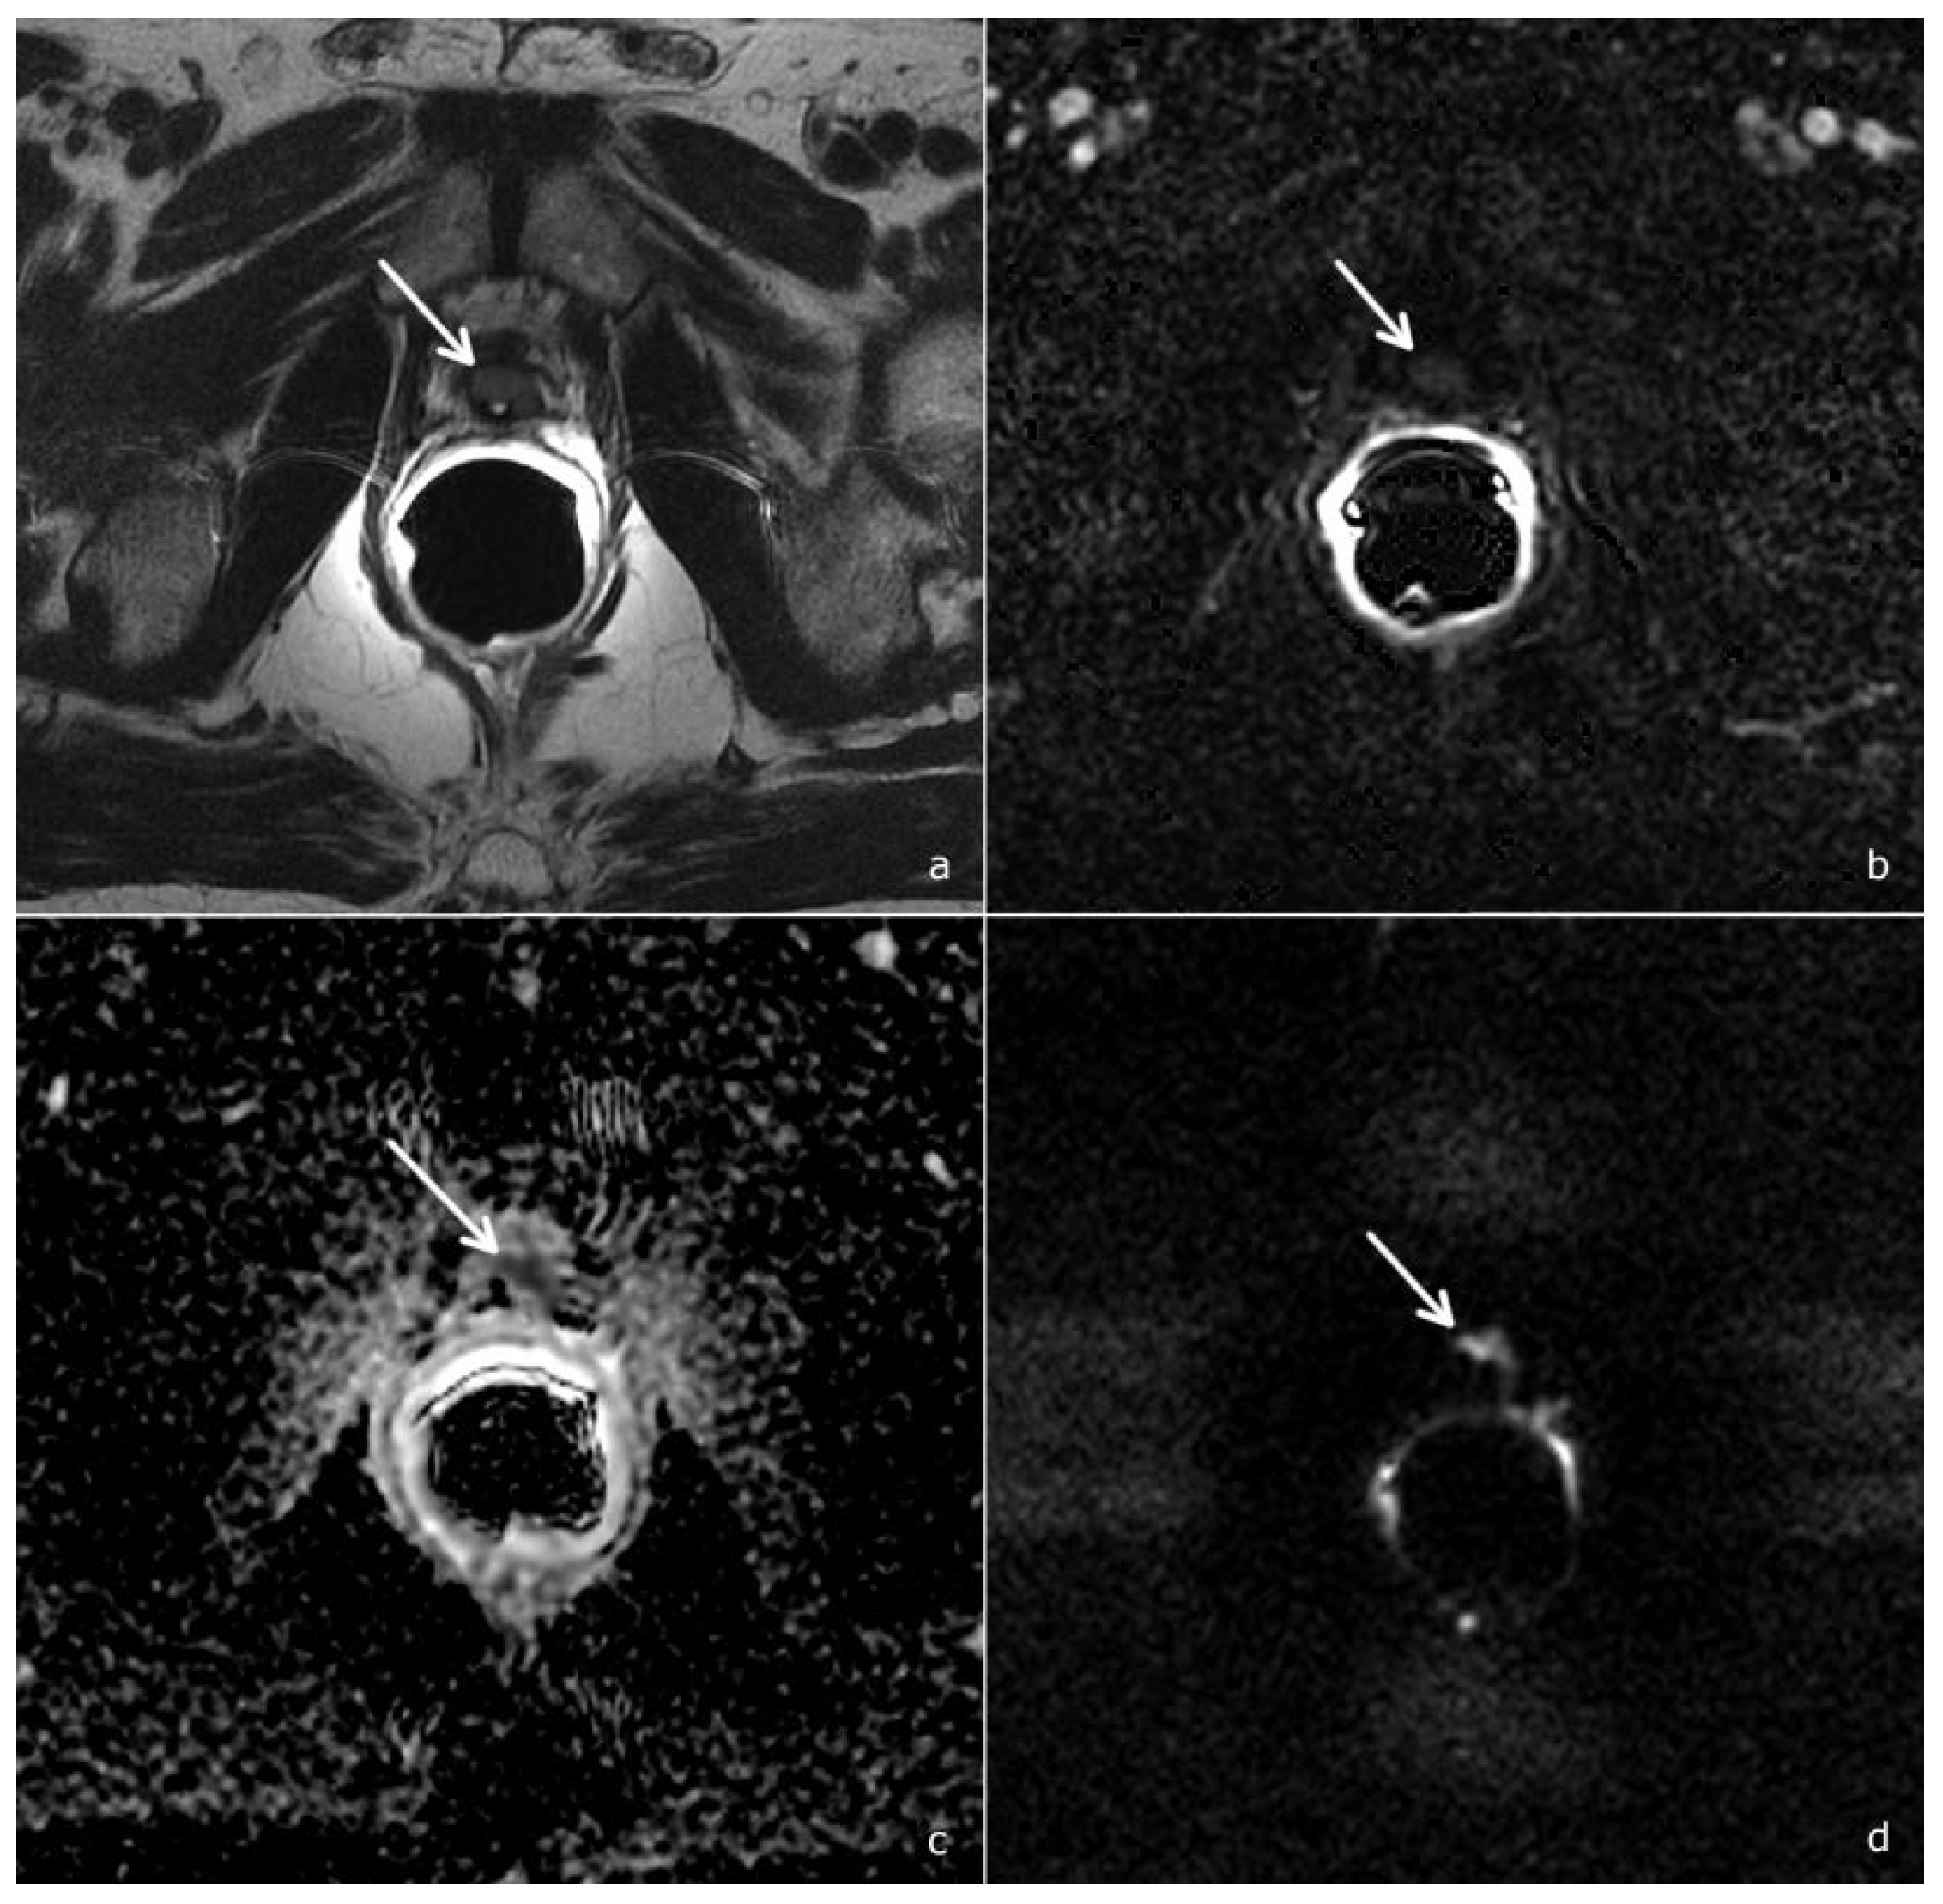

- Diffusion-weighted imaging (DWI): a single-shot echo-planar sequence with a high b-value (2000 s/mm2) and another single-shot echo-planar sequence with two different b-values (50 and 1000 s/mm2), this latter for the calculation of the apparent diffusion coefficient (ADC) map.

- DCE acquisition: three-dimensional (3D) T1-weighted Time-of-Flight Spoiled Gradient-Recalled sequence on the axial plane during the intravenous injection of a gadolinium-based contrast agent at a flow rate of 3 mL/sec followed by 15 mL of saline solution. The 3D data sets were acquired with a 10 s temporal resolution; the acquisitions before the contrast agent administration were analyzed to detect foci of hemorrhage.

- Gaudiano, C.; Ciccarese, F.; Bianchi, L.; Corcioni, B.; De Cinque, A.; Giunchi, F.; Schiavina, R.; Fiorentino, M.; Brunocilla, E.; Golfieri, R. The role of MRI in the detection of local recurrence: Added value of multiparametric approach and Signal Inten-sity/Time Curve analysis. Arch. Ital. Urol. Androl. 2022, 94, 25–31. [Google Scholar] [CrossRef]